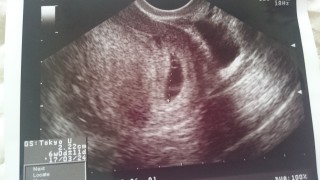

2年半の不妊治療、9回の体外授精でやっと妊娠しました。前回心拍確認後流産しているので、心配ですが、今回は出血も腹痛もなく、胎のうも前回より大きいです。先生にも、大丈夫そうですねと言われました。 胎芽の大きさは計って貰えませんでしたが、元気に動く心拍が確認できました。胎のうの大きさ2.2センチです。元気に大きく育ってね。あなたに会えるのを楽しみにしてます。

生理予定日の2週間後に初めて受診☆ 赤ちゃんと心拍を旦那さんと一緒に確認して感動(´:ω:`) 心臓がピクピク動いてて可愛かったです。 次の検診が楽しみです。

初投稿! 心拍確認されました♡ぴこびこ動いててすでにかわいい♡ が、なんと子宮頸がんの疑いが。。(;_;)こわいなぁ。。なにもないといいな~

今朝少量の茶オリがでたため、受診しました。 四日前は胎嚢しかみえなかったのにこの四日間で心拍確認できました! 茶オリも心配いらないようです。 安心しました!!